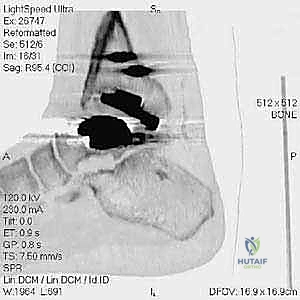

- التصوير المقطعي المحوسب (CT Scan): وهو الأداة الذهبية لتقييم "المخزون العظمي" (Bone Stock). يوضح بدقة حجم الأكياس العظمية ومقدار العظم المفقود الذي سيحتاج لترقيع.

* دمج الكاحل (Ankle Arthrodesis): إذا كان التآكل العظمي هائلاً ولا يسمح بتركيب مفصل جديد، يتم إزالة المفصل الصناعي ودمج عظمة الساق مع عظمة الكاحل باستخدام مسامير وصفائح معدنية وطعوم عظمية.

الخطوة الرابعة: تنظيف العظم والترقيع (Debridement and Bone Grafting)

يتم تنظيف الأنسجة الملتهبة والأكياس العظمية. ونظراً لأن مفصل (Agility) يترك فراغاً كبيراً بعد إزالته، يتم استخدام طعوم عظمية (Autograft من حوض المريض أو Allograft من بنك العظام) لملء الفراغات وبناء أساس قوي.

الخطوة الخامسة: تركيب المفصل الجديد أو الدمج

يتم إدخال المفصل الجديد المخصص للمراجعة، والذي يحتوي غالباً على سيقان (Stems) تدخل عميقاً في عظمة الساق وعظمة الكاحل لضمان الثبات الميكانيكي. في حال وجود كسور في الكعب، يتم تثبيتها في هذه المرحلة.